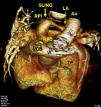

En el estudio mediante TC multidetector (Toshiba Aquilion, 64 detectores®) se confirmó el diagnóstico de sling de la arteria (fig. 2). La reconstrucción 3D permitió una mejor identificación de la relación espacial entre las ramas pulmonares, aorta, vena cava superior y vena innominada; así como el anillo vascular con el trayecto estenótico de la rama pulmonar izquierda (fig. 3).

TC-3D: Reconstrucción 3D que permite una mejor identificación de la relación espacial entre el tronco pulmonar (TP), la rama pulmonar derecha (RPD), rama pulmonar izquierda (RPI), aorta (Ao), vena cava superior (VCS) y vena innominada (VI); así como el anillo vascular (sling) con el trayecto estenótico de la rama pulmonar izquierda. Ligamento arterioso (LA).